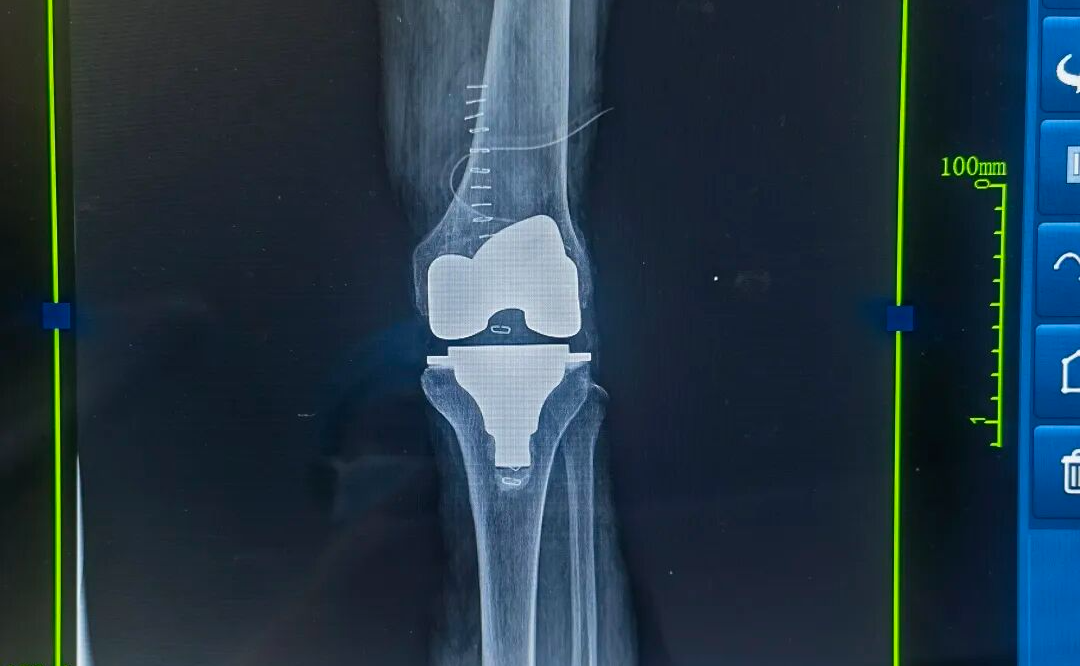

近期,患者疼痛症状急剧加剧,常规口服药物及理疗措施均无法有效缓解疼痛,夜间因疼痛难以入眠,生活质量受到严重影响。来到我院后,做了全面细致地检查与评估,以“左膝关节重度骨性关节炎”收住入院。结合患者病情及检查结果,我们决定为其优先实施左膝关节置换术。

左膝关节置换手术成功完成

经过术前的精心准备,刘海亮主任团队为其顺利施行了左膝关节置换术。膝关节置换手术只是 “万里长征第一步”,科学康复才是决定患者能否重获行动力的关键。在康复医师指导和医护人员的精心护理下,患者很快便能扶助行器下床行走,膝关节功能恢复迅速。